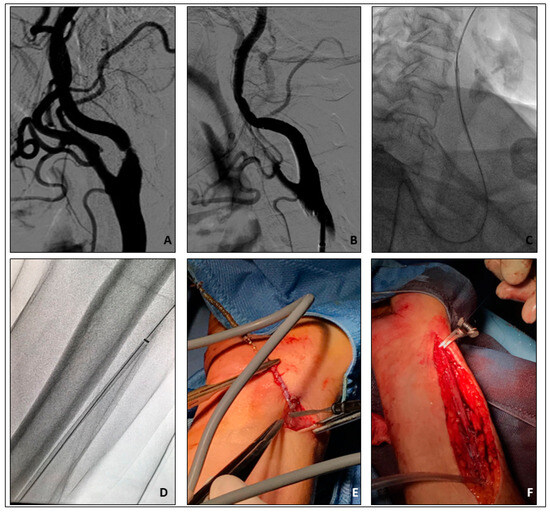

- Rescue retrieval of a disconnected distal cerebral embolic protection device

- Brief Case description: